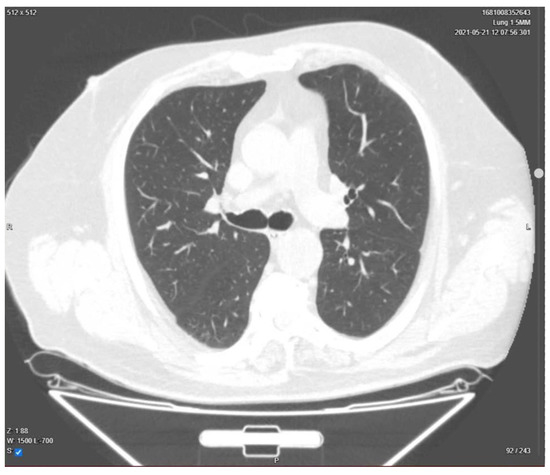

| Presentation | A 52-year-old man presented in the ER with malaise, fever, severe cough, tachypnea, tachycardia, and dyspnea, which started 2 days before the presentation. Upon rapid assessment, the patient had low oxygen saturation and showed signs of respiratory failure. The decision was made to transfer the patient to the ICU after preliminary radiological examination. |

| Day 23 | Lung CT was performed for pulmonary re-evaluation. |